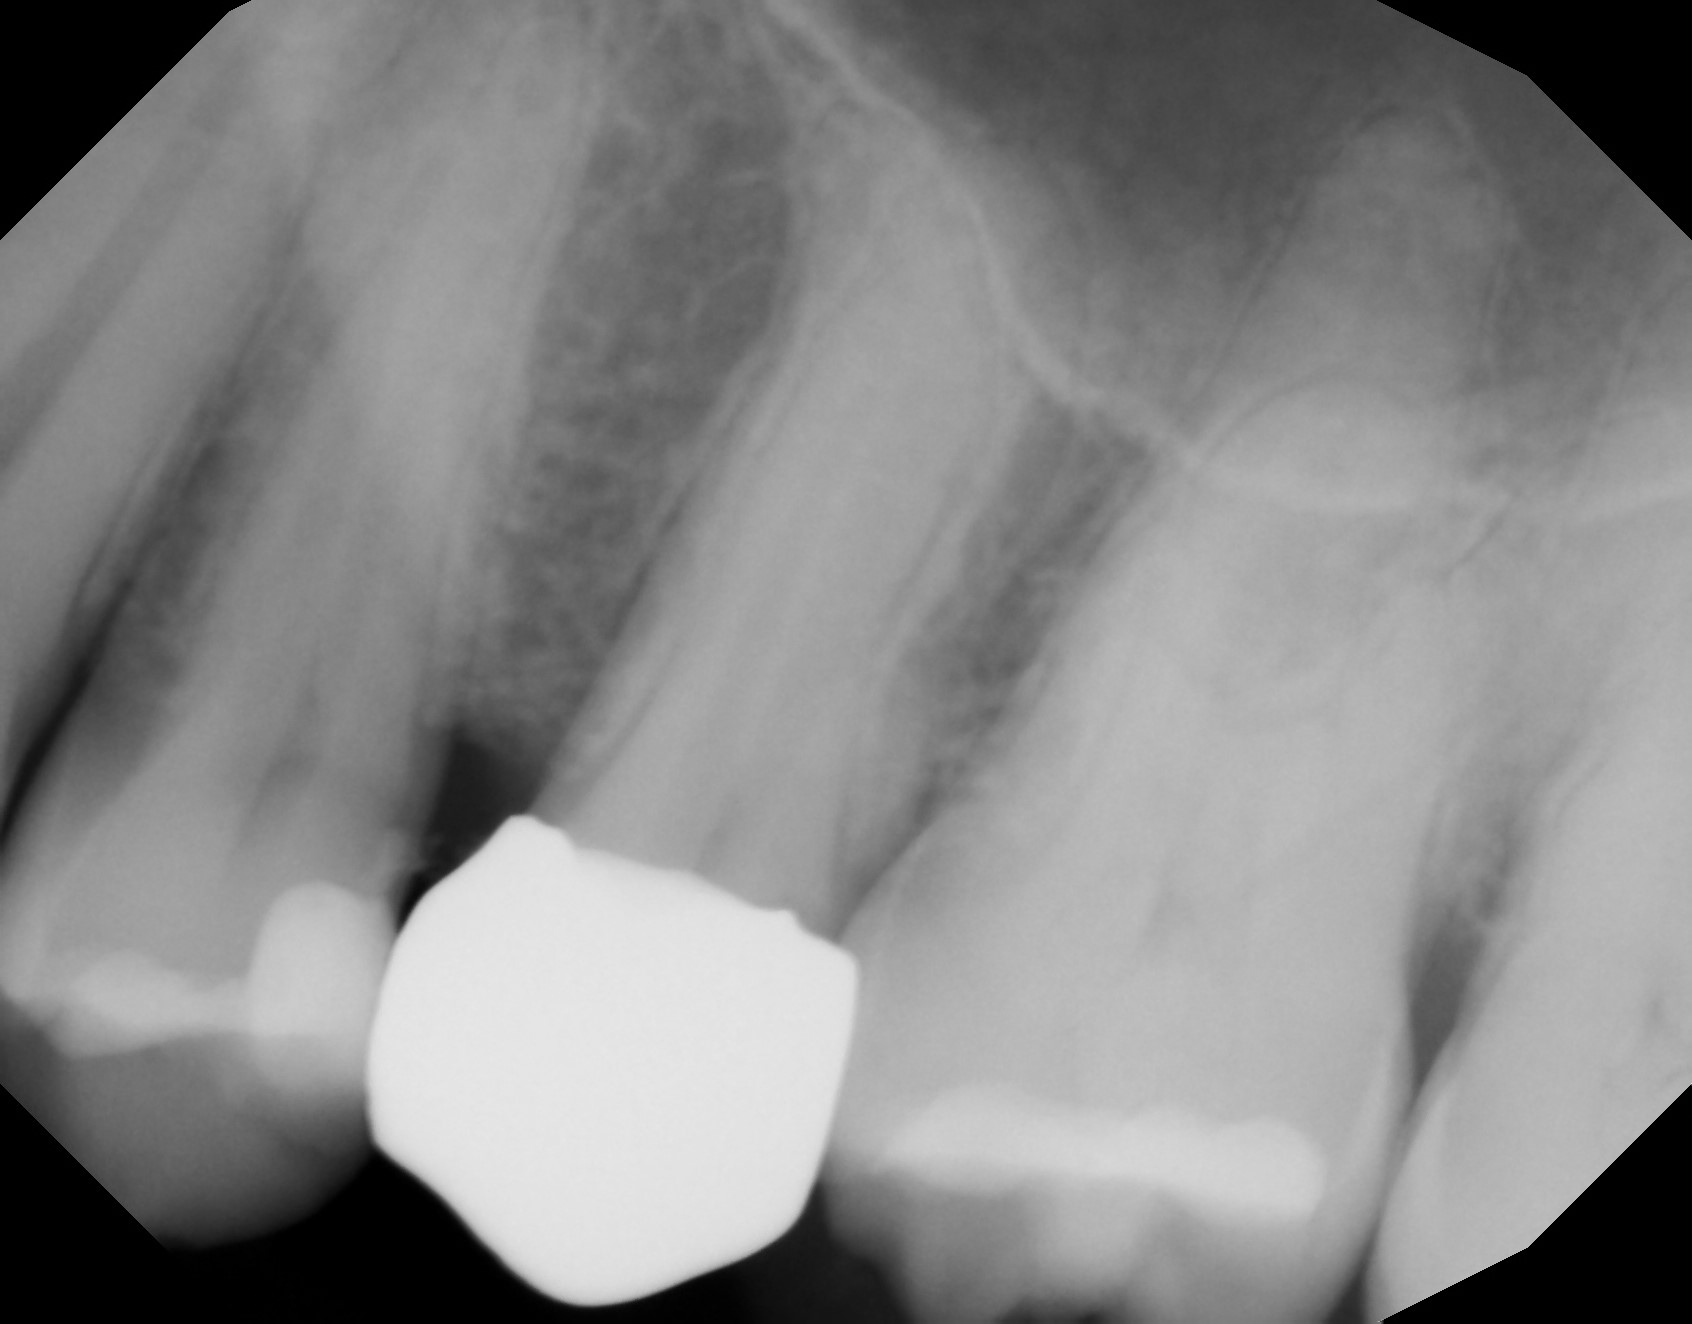

A 57-year-old male patient presented with the complaint of sensitivity to temperature in the maxillary left quadrant. A radiograph was taken (Fig. 2), and deep caries was noted in the second premolar with possible pulpal involvement. Periapical pathology was not noted radiographically. The tooth was tested with cold to verify that the pulp was vital. A mild reaction was noted when cold was applied that immediately resolved when cold was removed from the tooth, indicating that the tooth was vital. The patient was advised that endodontic treatment may be required if a large pulpal exposure resulted from caries removal or if the tooth became symptomatic after treatment. Should a small pulpal exposure be noted or caries removal result in thin dentine over the pulp, laser treatment would be utilised prior to core placement to sterilise the area and avoid pulpal infection developing. A core build-up and complete crown were planned for the tooth. The patient accepted the treatment recommendations.

The patient was seen on recall at four weeks after restoration, and a periapical radiograph was taken (Fig. 9). No periapical radiolucency was noted, and the patient continued to report a lack of sensitivity to temperature or occlusion, indicating successful laser treatment of the pulpal exposure.

Fig. 9: Periapical radiograph taken four weeks after restoration placement, demonstrating an absence of periapical pathology.